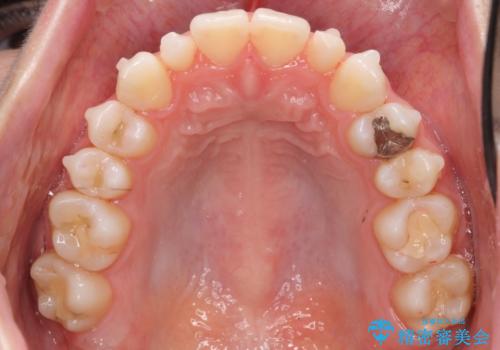

前から2番目の歯が小さく、細くとがった形になっていました。

大きくしようにも、幅が少ない上に、また、内側に入ってしまっているため、矯正治療で前歯を並べてからセラミックでかぶせることにしました。

先に矯正治療をすることで、下の前歯を内側に入れることができ、上の歯のセラミックの幅や厚みを取ることができました。